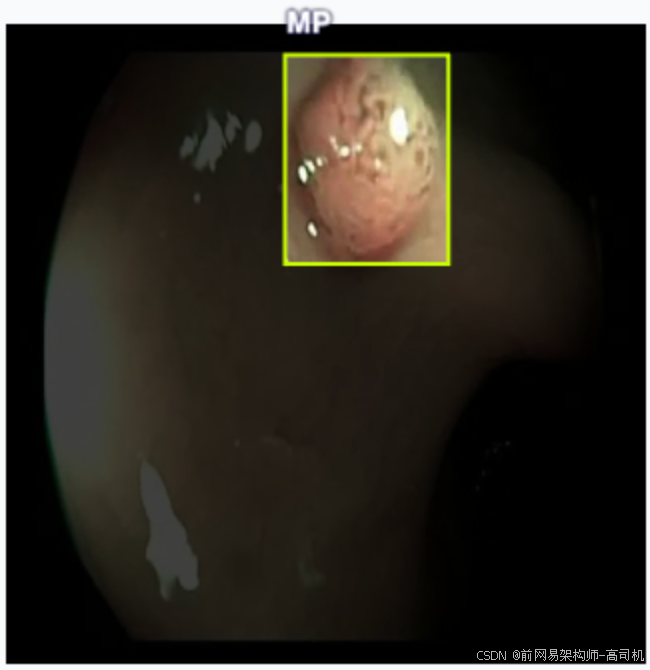

- MP:需结合内镜类型区分,核心有 2 类常见含义

(1)消化道内镜:多为「增生性息肉(Hyperplastic Polyp)」

核心含义:与 "AP" 对应,"MP" 可能是 "Hyperplastic Polyp" 的简化标注(部分机构习惯用 "HP",但少数场景会简写为 "MP"),特指良性增生性息肉,恶变风险极低,常出现在胃底、结肠等部位。

场景示例:胃镜报告 "胃底多发 MP,直径 0.2-0.3cm",即 "胃底有多个增生性息肉,大小 0.2-0.3 厘米"。